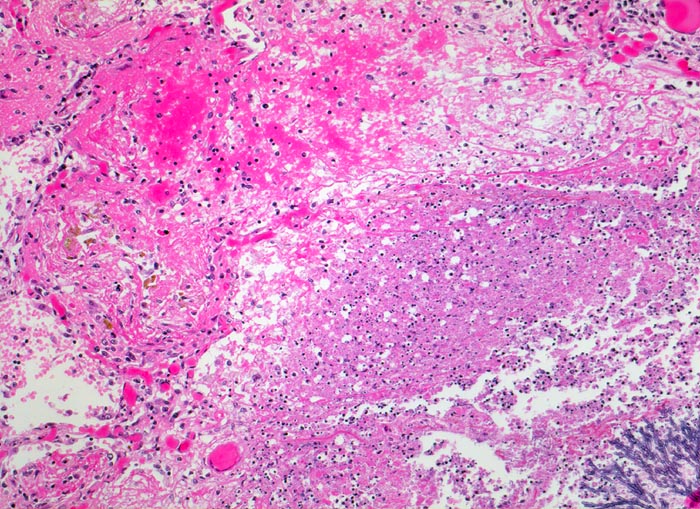

Morphologische Merkmale:

• Multiple Herde mit zentraler Nekrose und hämorrhagischem Randsaum.

• Pilzmyzelien, zerfallende neutrophile Granulozyten und Erythrozyten im Zentrum der Herde.

• Kräftig gefärbte Pilzhyphen mit 45° Verzweigungen.

• Hämorrhagischer Randsaum um die Nekrose: Hyperämische Alveolarwandkapillaren. Alveolen angefüllt mit Blut, Fibrin und Alveolarmakrophagen.